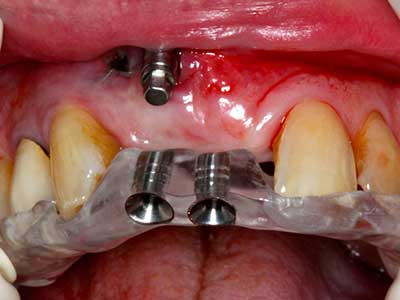

Пиезохирургията има допълнителни предимства при събиране на костни блокове. В допълнение към високата прецизност при остеотомията, описана по-горе, употребата на фините режещи накрайници значително намаляват загубата на материал. Голяма загуба на материал по време на събиране може да се очаква с дебелите накрайници, особено при употреба на борери Линдеман (Lakshmiganthan, Gokulanathan et al. 2012). Базалното разделяне, което е необходимо, особено за присадка на блок при ретромолар, е улеснено от специално създадени правоъгълни триони. В резултат на това, пиезохирургията е разглеждана като прецизна, улеснена и безопасна процедура за събиране на костни блокове в ретромоларното пространство (Happe 2007) (Фиг. 1-12).

Индикация: Костно разделяне/ шиниране?

Костната тъкан е не само минерализирана структура, тя съдържа и съществено количество колагенови влакна. Това означава, че тя има не само добра компресивна сила, но и известна степен на гъвкавост, която може да се възприеме като предимство при извършване на костна аугментация. В класическата процедура по разширяване чрез костно разделяне, атрофиралият алвеоларен гребен е разделен надлъжно и внимателно разширен след достигане на подходящата остеотомна дълбочина (Фиг. 13-16), в идеалния случай без допълнително отстраняване на периостеума (Brugnami, Caiazzo et al. 2014, Stricker, Fleiner et al. 2014). Системите с винт и пластини с увеличаване на разстоянието при разширяване са доказали ефективността си при разделяне на двете костни ламели, оставайки под прага на фрактурите. В общи линии, оставащата ширина на костта от поне 3–4 mm е задължителна (Chiapasco, Zaniboni et al. 2006), за да се гарантира добра гъвкавост и достатъчно костно покритие за бъдещото поставяне на импланти. Ако е необходимо, вертикалната остеотомия на едната или двете страни може да подобри гъвкавостта. Комбинацията с допълнителни техники за аугментация, особено в букалната страна, е описана като алтернатива на класическата техника.

Процедурата по разделяне е атравматична и няма голяма загуба на пространство, използвайки пиезотриони, и няма значителна разлика между импланти в разделени челюсти и импланти в алвеоларния гребен без костен дефицит (Chiapasco, Zaniboni et al. 2006, Danza, Guidi et al. 2009). Въпреки това, важно е да има достатъчно и продължително охлаждане, особено при ограничено и дълбоко разделяне, за да се избегне термичен стрес в апикално-остеотомните зони.